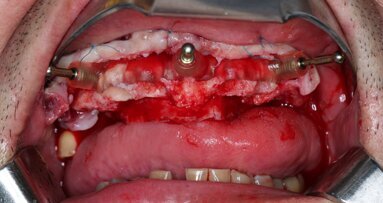

Furthermore, undersized drilling with continuous bone density assessment according to the operator’s own experience is mandatory to achieve the highest insertion torque, taking account of the biological bone situation and the mechanical properties of Roxolid. In this case, six implants (Straumann BLT, Regular Neck, Roxolid, SLActive, four of ⌀ 4.1 mm and two of ⌀ 4.8 mm) were placed with the handpiece at 45 N cm, with a final manual setting and monitoring of the insertion torque (Figs. 5 & 6). Careful orientation of the Loxim orientation marks is mandatory to maintain the desired parallelism of the SRA prosthetic screws.

After final implant seating, BLT Type 54 SmartPegs from Osstell were placed on each implant, and the ISQ level was measured and recorded at implant connection level. Values between 75 and 85 out of 100 were obtained, confirming the immediate loading possibility on all the implants (Figs. 7 & 8).

SRAs were connected to all of the implants: two 17º Type A angulated SRAs were placed on the anterior implants to correct the angulation for immediate prosthetic rehabilitation. Straight SRAs were placed on the remaining implants (Fig. 9). New ISQ levels were measured at abutment level using the convenient BLT Type 25 SmartPegs. It is important to record the ISQ level at implant and abutment level in the surgery so that the values can be extrapolated in future Osstell readings at SRA level.